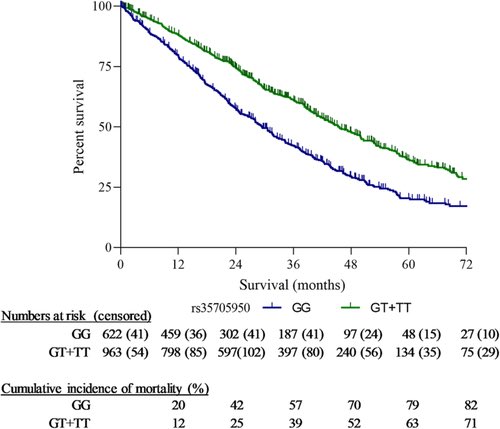

MUC5B rs35705950 minor allele associates with older age and better survival in idiopathic pulmonary fibrosis.

Respirology.

2022,

ISSN: 1323-7799,

PMID: 36571111,